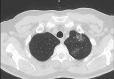

Results: One patient (0.5%) showed typical CT features for COVID-19 pneumonia; 12 patients (5.5%) were reported as indeterminate, and eight (3.7%) were reported as atypical for COVID-19 pneumonia. Only one of the three patients with positive RT-PCR had abnormalities on CT. When RT-PCR tests were taken as reference, the sensitivity, specificity, and accuracy of chest CT in showing COVID-19 infection in asymptomatic patients were 33.3%, 90.7%, and 90.0%, respectively.

Conclusion: Chest CT screening for COVID-19 has a very low yield in asymptomatic preoperative patients and shows false-positive findings in 9.2% of cases, potentially leading to unnecessary postponing of the surgery.